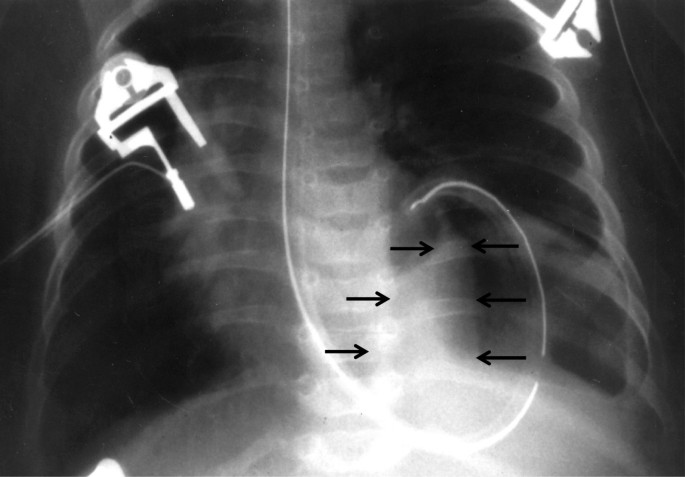

Анатомия диафрагмы и треугольника Бохдалека